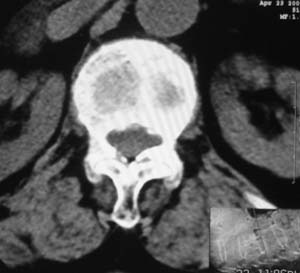

患者,女,72岁,胸背部疼痛3月余,无明显外伤史。曾应用局部封闭、非甾体类止痛药治疗效果不明显,近来疼痛缓解频感背困,平卧缓解,近日行ct检查发现胸12椎体病变,烦请同道发表意见,诊断什么?有何治疗经验!谢谢!!!

标绘图示:第十二胸椎级第一腰椎椎体楔形改变。ct扫描示:第十二胸椎椎体骨质结构紊乱,并可见一囊状低密度影,边缘可见硬化,椎体皮质完整。

考虑:第十二胸椎陈旧性骨折、许莫氏结节。